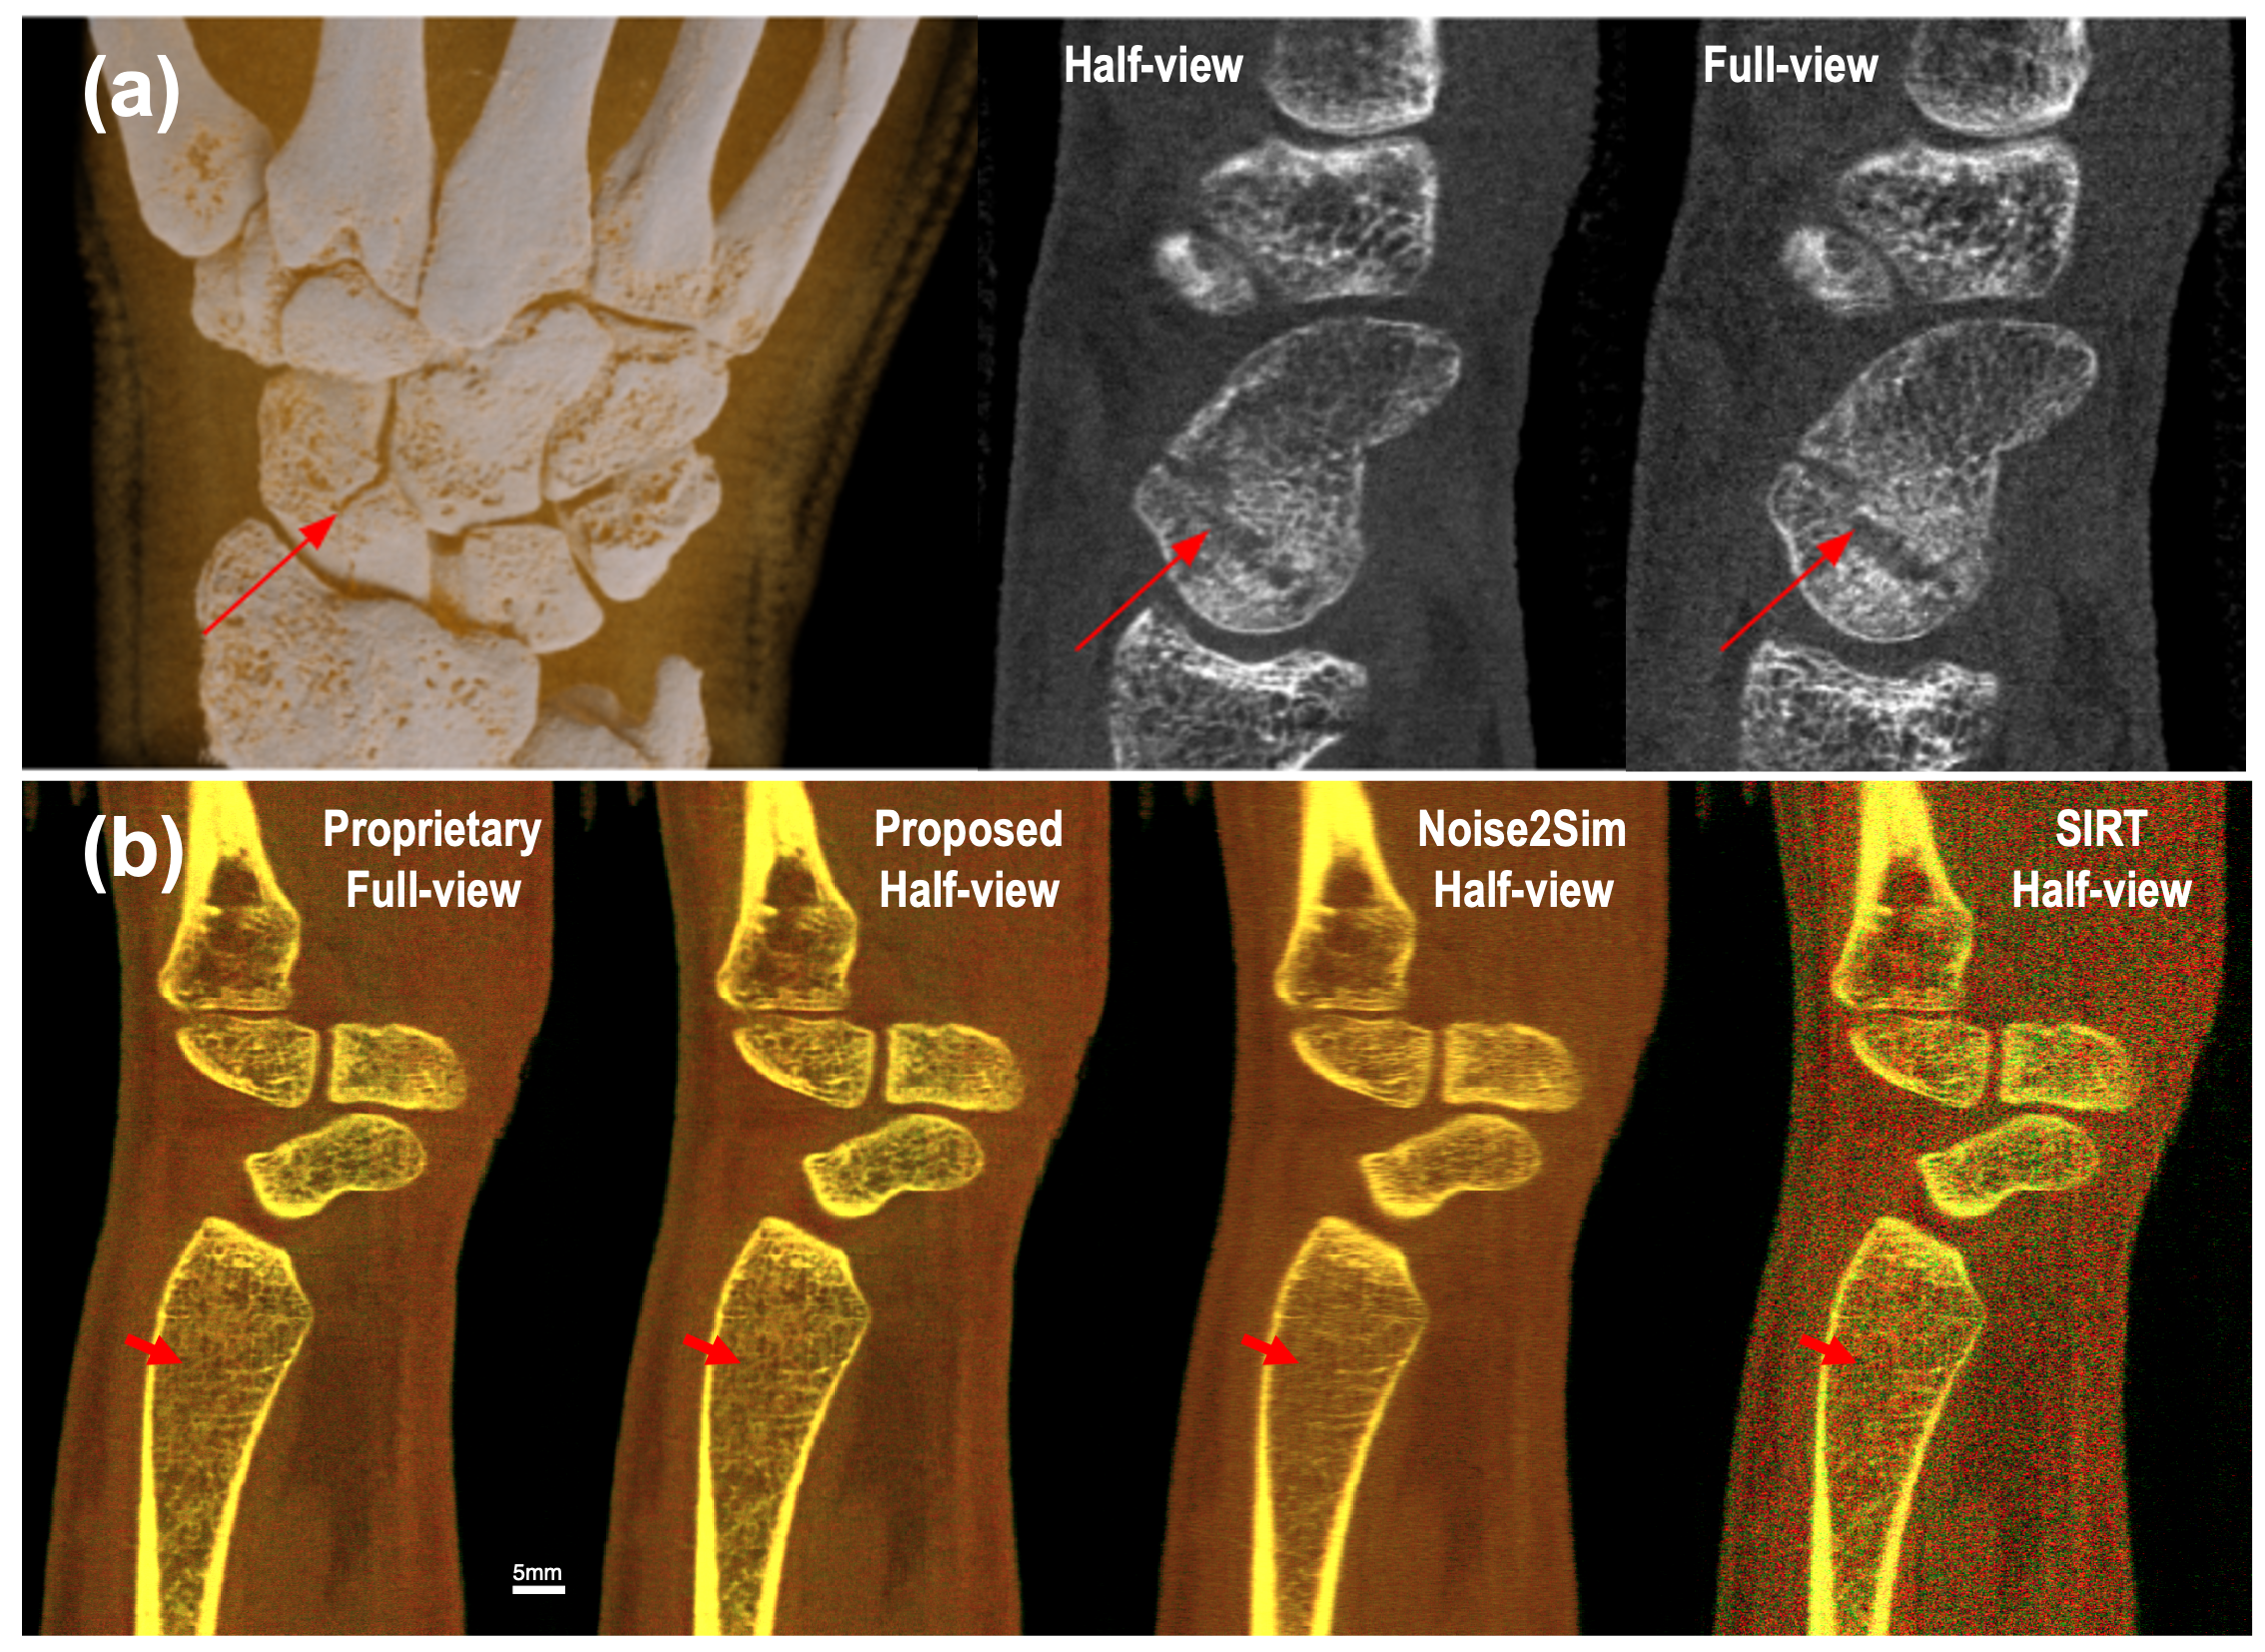

The radiologists were presented with 500 images from each patient (three energy bins 740keV740𝑘𝑒𝑉7-40keV7 - 40 italic_k italic_e italic_V, 5060keV5060𝑘𝑒𝑉50-60keV50 - 60 italic_k italic_e italic_V and 70118keV70118𝑘𝑒𝑉70-118keV70 - 118 italic_k italic_e italic_V) in the axial, coronal and sagittal formats. The sagittally reformatted images reconstructed using both methods and 3D rendering image using the standard method are shown in Fig. 7(a). The images were reviewed using InteleViewer (Intelerad Medical Systems). The image metrics assessed in the study were based on the “European guidelines on quality criteria for CT” for bones and joints [49]. The images were assessed on seven image quality criteria, including the visibility and sharpness of the cortical and trabecular bone, adequacy in soft tissue contrast for the visualisation of tendons, muscle and ligaments, as well as the effect of image noise (quantum noise) and artifact on the image quality.

Additionally, we also compare our result with that obtained by applying the state-of-the-art unsupervised learning method Noise2Sim [27] to the multi-channel reconstructions using 320 SIRT iterations for each channel. Despite significant enhancement over SIRT reconstruction from half-view dataset, Noise2Sim results demonstrate insufficient image quality (suffering from image blur and loss of fine structures) as shown in Fig. 7(b), hence, they are excluded from the reader study.

Refer to caption

Figure 7: Sagittal reformat of a wrist joint reconstructed using standard and proposed methods respectively. (a) From left to right are 3D rendering of standard reconstruction, half-view and full-view images of channel 50-60keV. The arrow points to scaphoid fracture. (b) Color visualization of our three-channel reconstruction via linear blending [50] in reference to standard full-view result and noise2sim half-view result. Our result demonstrates high fidelity in both spectral values (same color tone and brightness as the full-view reference) and spatial structures (sharp and accurate fine details as pointed by the red arrow).